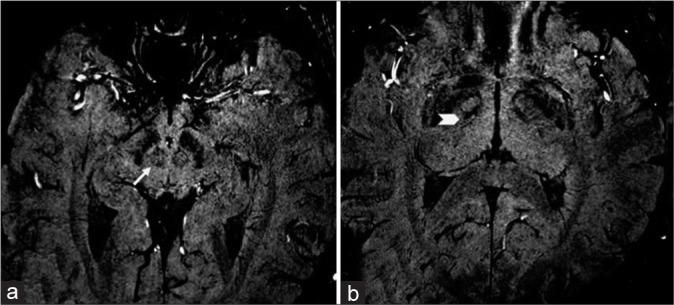

Patients of advanced Parkinson's disease were prospectively followed for clinical details, motor severity scores, and radiological evaluation. Volumes of the STN and RN were measured on susceptibility weighted imaging, coronal sections in 3T MRI and were correlated with demographic and clinical features.

对晚期帕金森病患者进行前瞻性随访,记录临床细节、运动严重程度评分及影像学评估。在3T MRI的冠状位上,通过磁敏感加权成像测量STN和RN的体积,并将其与人口统计学和临床特征相关联。